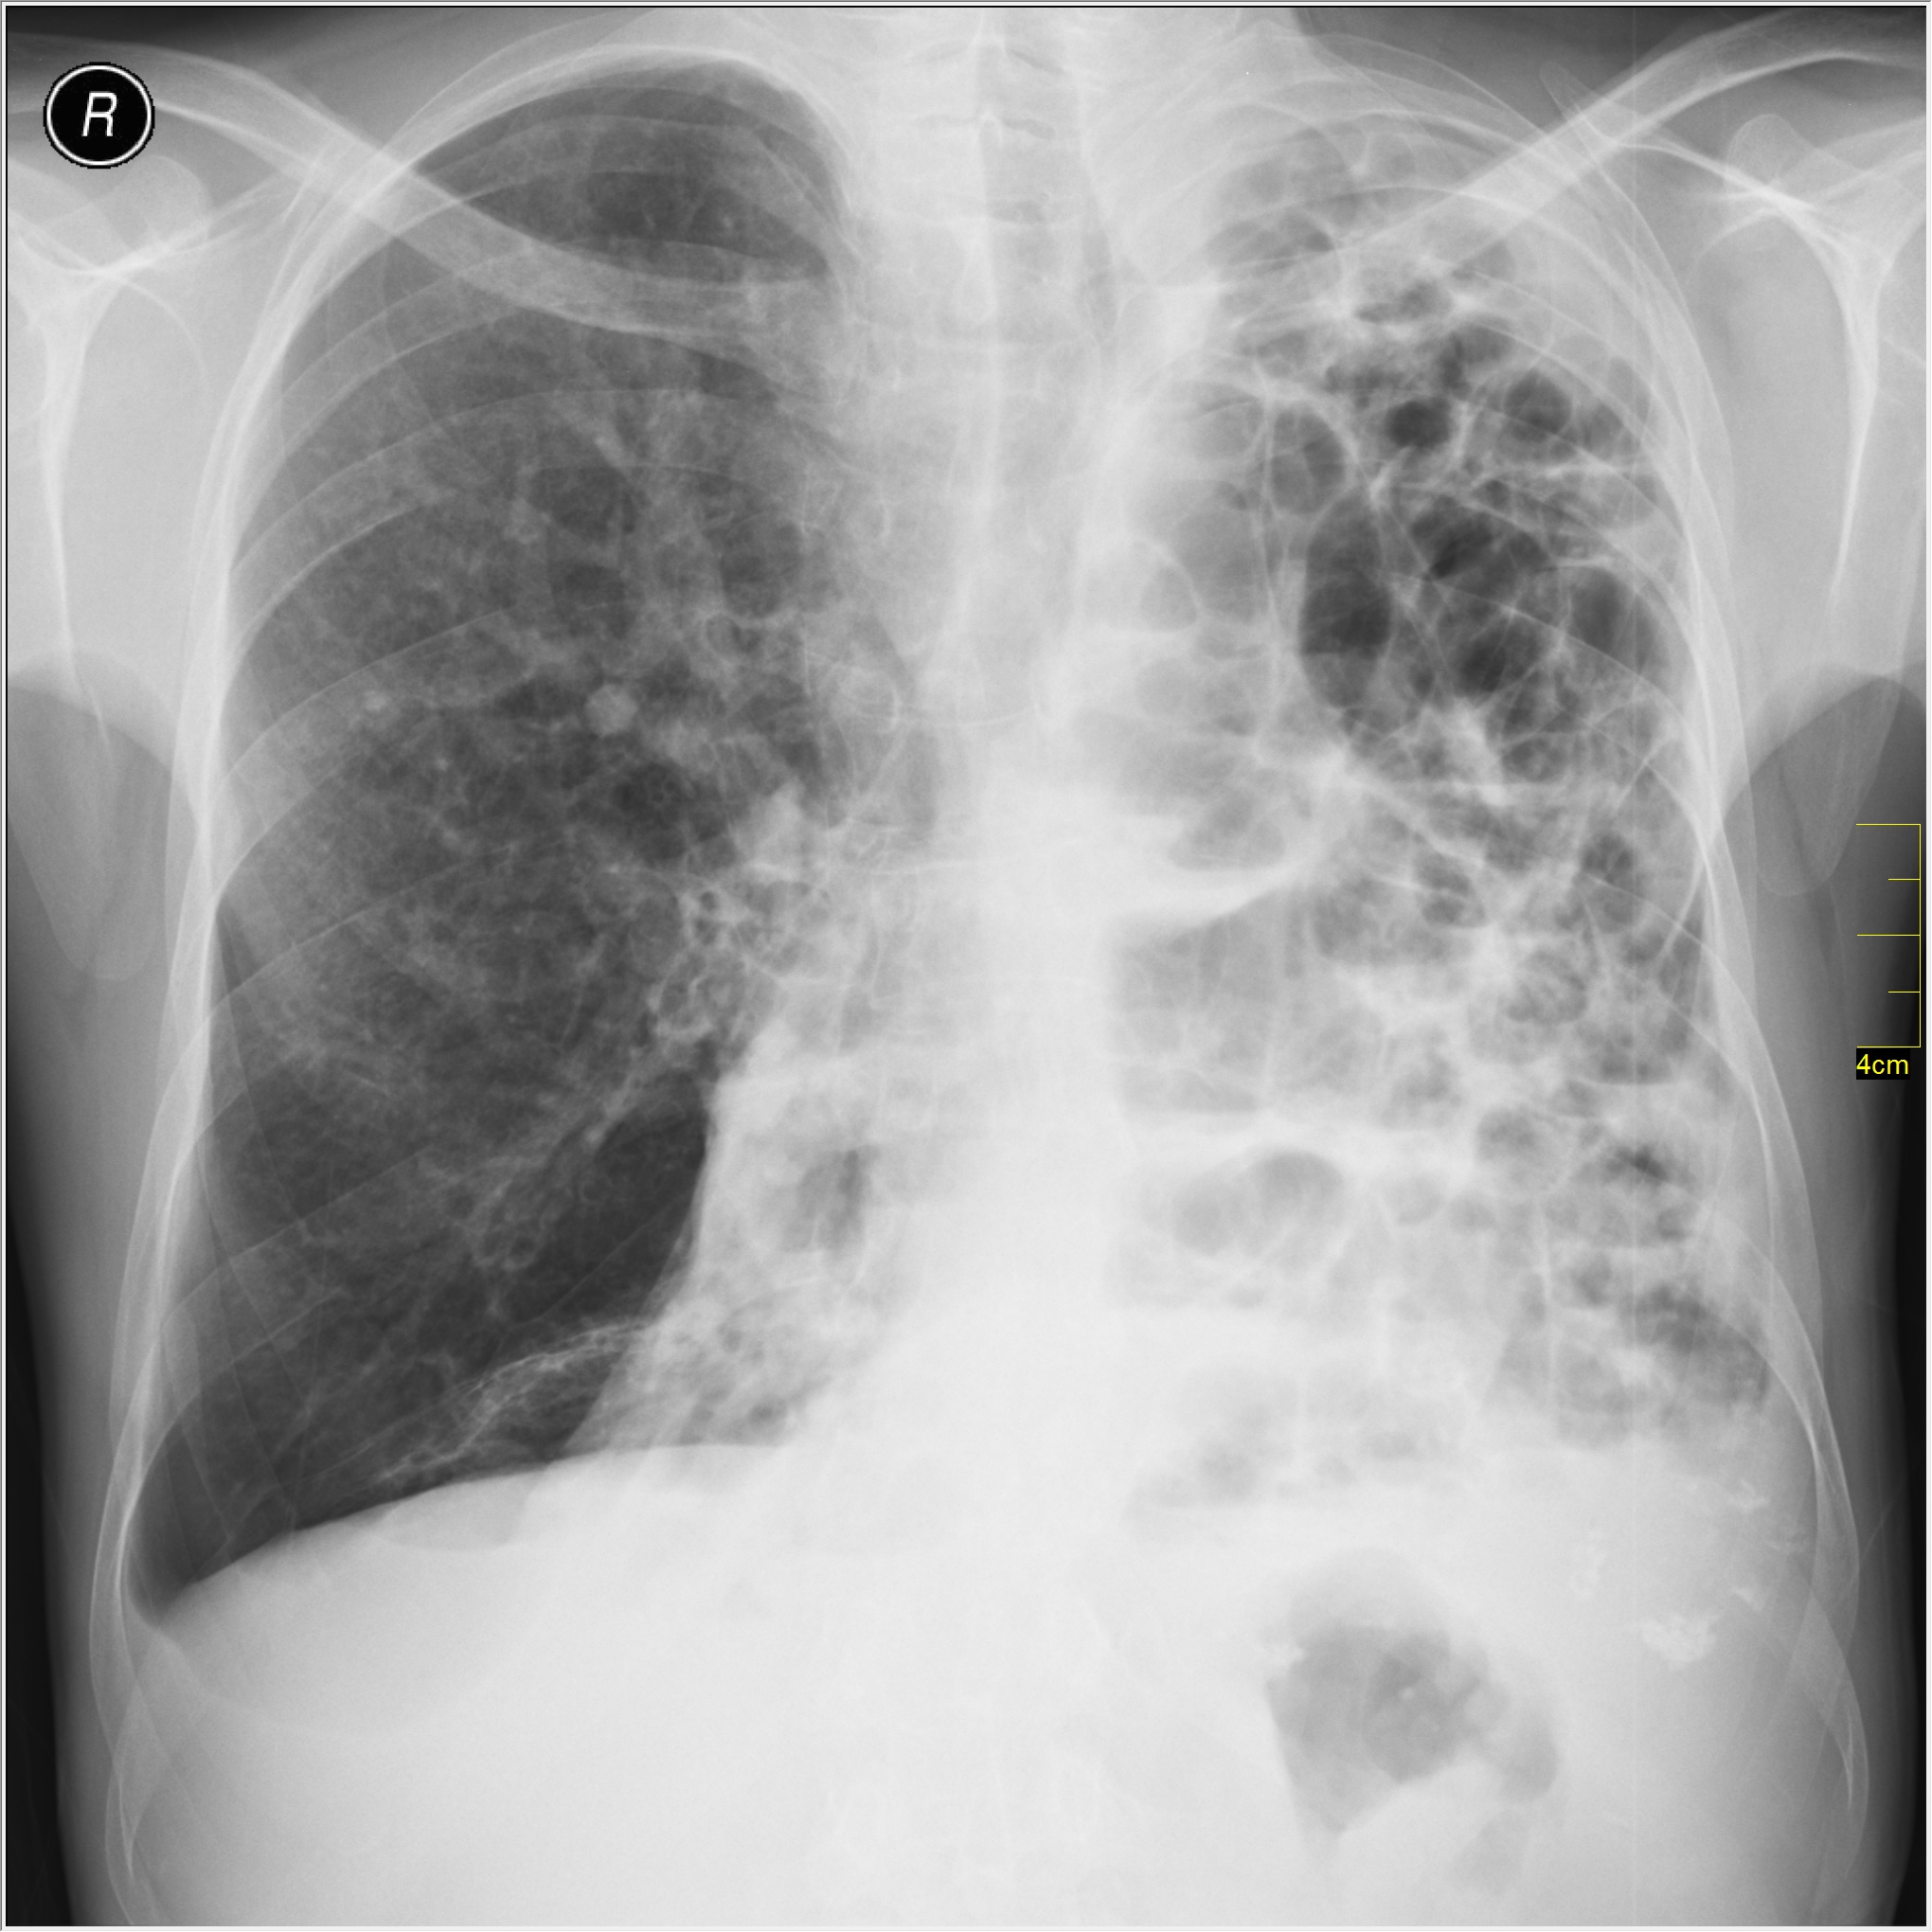

Снимок легких при туберкулезе является важным методом диагностики этого заболевания. На рентгеновских снимках можно увидеть изменения в легких, которые свойственны туберкулезу.

Диссеминированный туберкулез на рентгенограмме

Диссеминированный туберкулез рентген

Диссеминированный туберкулёз лёгких рентген

Фотографии снимков легких при туберкулезе

В данной статье представлены многочисленные фотографии снимков легких при туберкулезе, чтобы помочь вам понять, как выглядят изменения легких на рентгеновских снимках при этом заболевании.